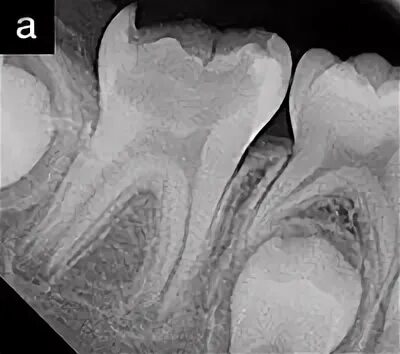

Лечение пульпита с несформированными